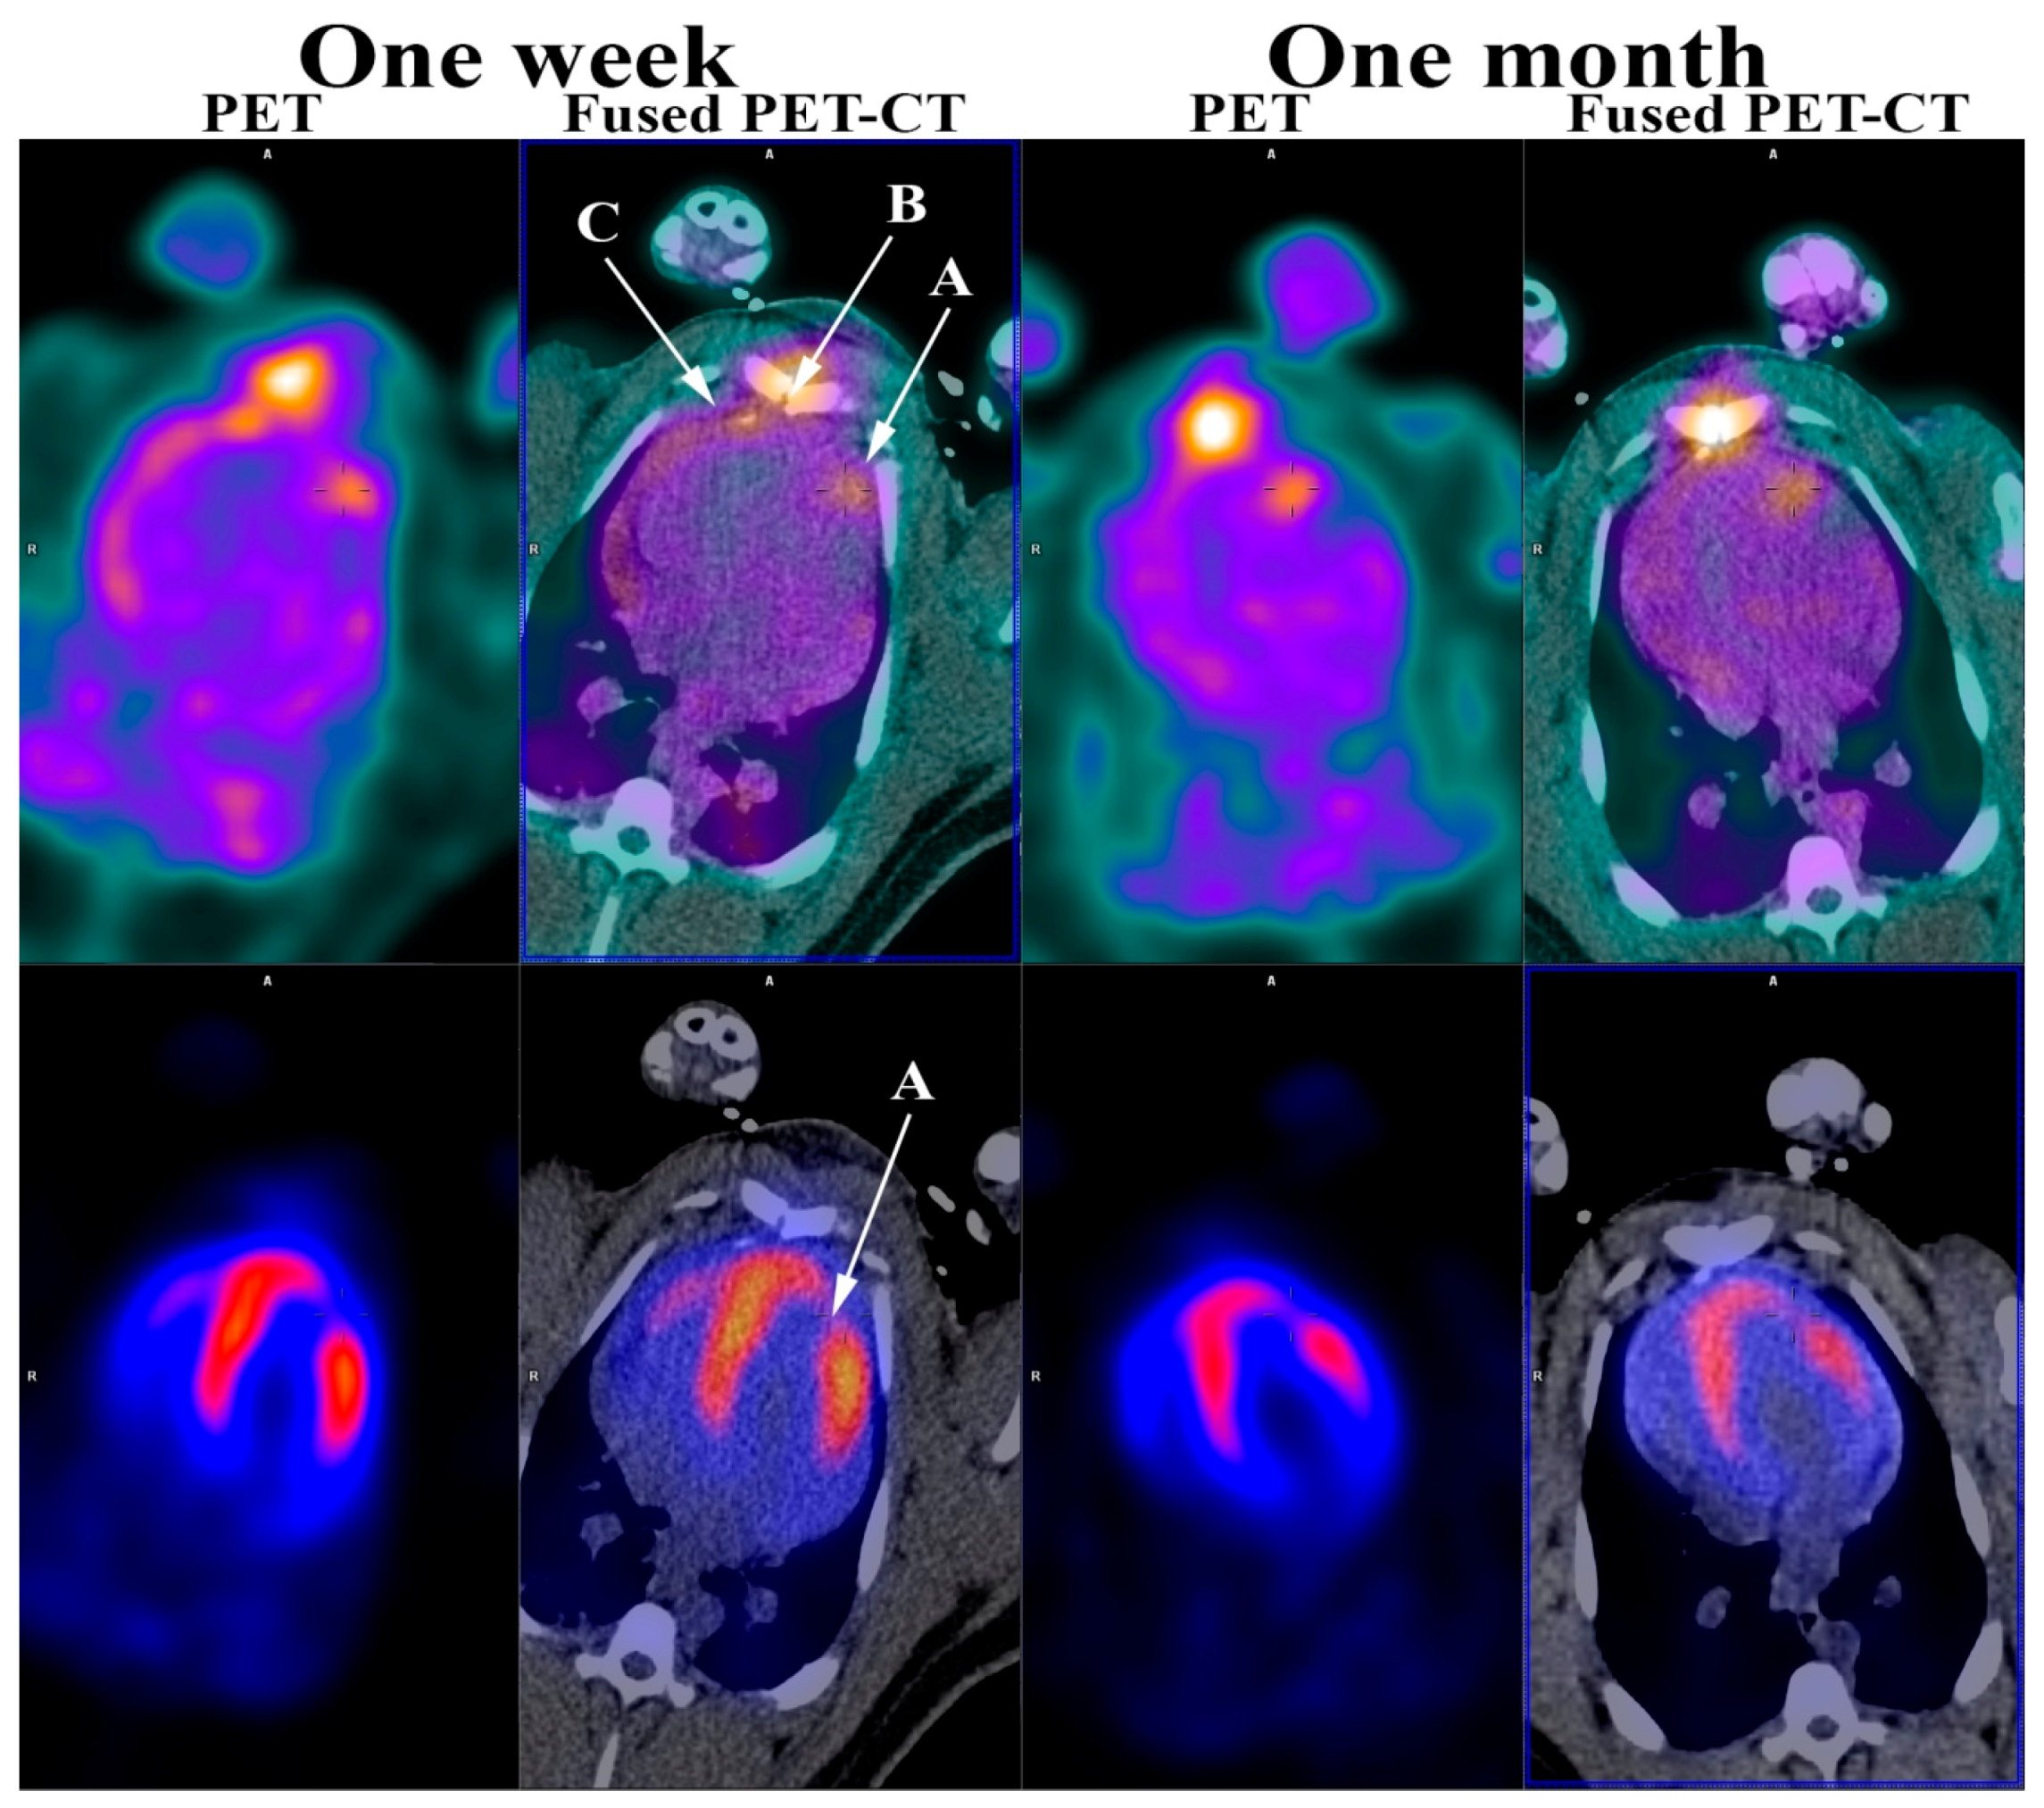

Figure 2.

RGD (top row) and 82Rb stress PET (bottom row) one week and one month after induced myocardial infarction. (A) Myocardial infarction; (B) Sternotomy; (C) Pericardium. As shown, the 82Rb stress PET (bottom row) showed a myocardial perfusion defect in the anterior wall of the left ventricle myocardium one week and one month after induced myocardial infarction confirming a myocardial infarction corresponding to an area supplied by the ligated branch from LAD. This myocardial perfusion defect was also present at rest (not shown). Furthermore, the RGD PET (top row) showed RGD uptake in the infarcted myocardium one week and one month following myocardial infarction. In addition, RGD PET showed RGD uptake in the sternum after sternotomy and pericardium, most likely due to the opening as part of the infarct induction procedure. As previously mentioned, most of the previous work in angiogenesis imaging have been done in smaller animals. The minipig heart and the human heart are very much alike, which makes the findings in this study even more encouraging and adds to the few, mostly very small, studies performed in human [16,17,18]. The perspectives are very intriguing and might permit the evaluation of new treatment strategies targeted towards increasing the angiogenetic response, e.g., stem-cell treatment.